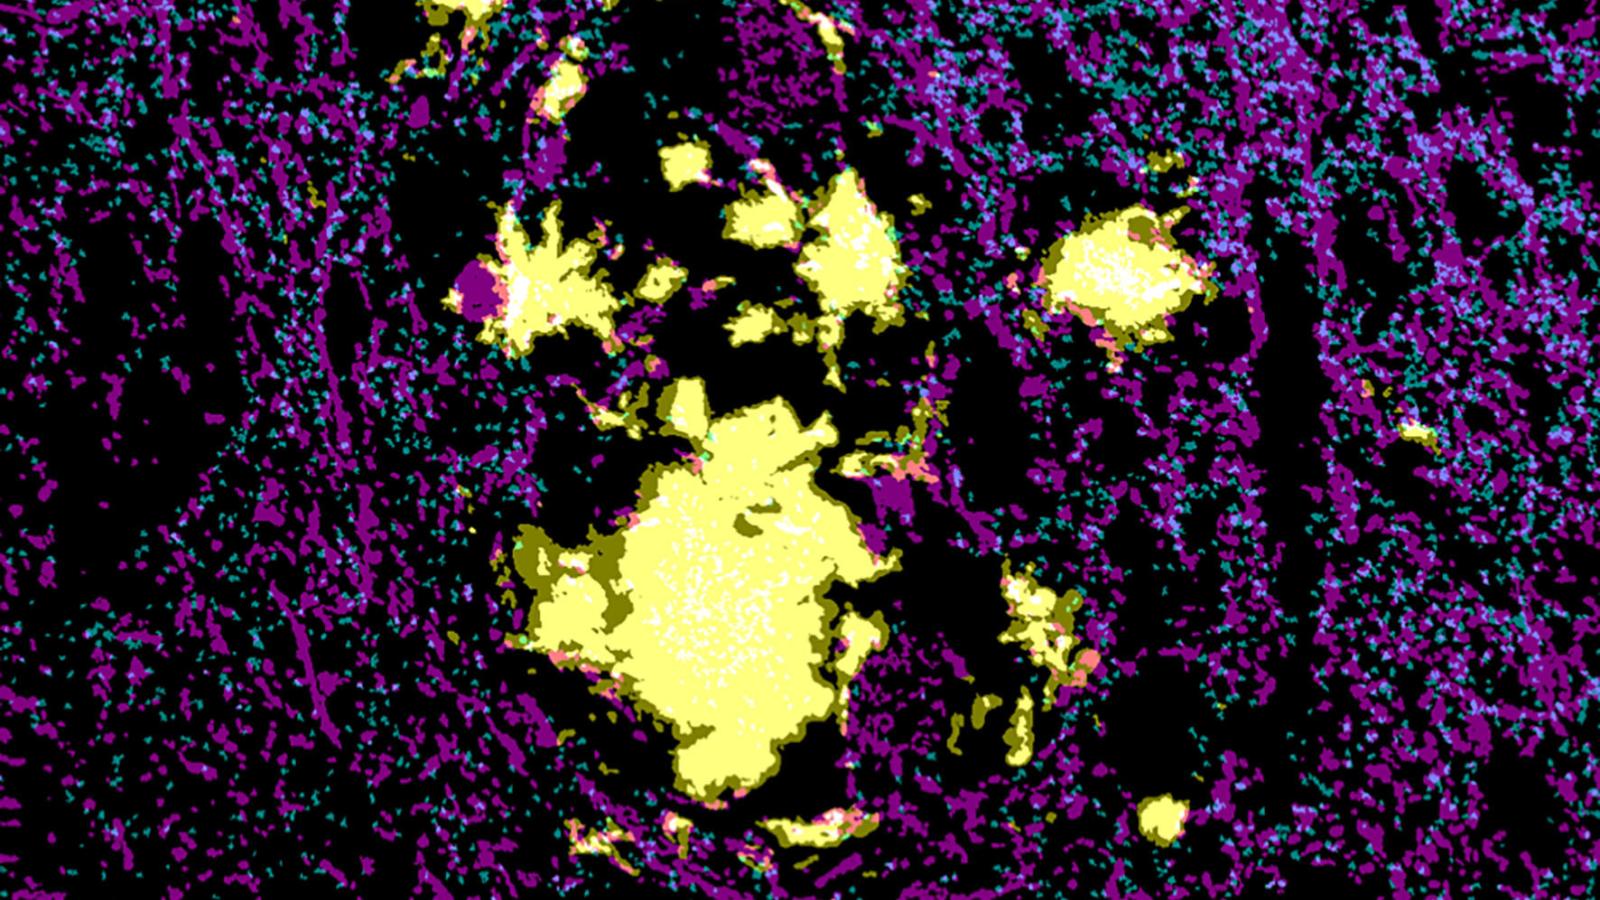

The team additionally investigated human post-mortem brain tissue from people with Alzheimer’s disease to determine translational relevance, showing a greater number of synapses near plaques were positive for the amyloid-beta in contrast to tau localisation which was not influenced by proximity to the plaques. This would suggest similar changes are observed between the model and human disease.